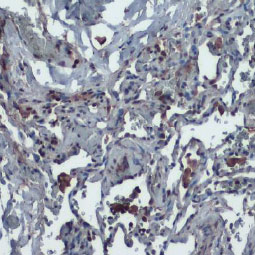

| 动物病毒的感染是通过病毒与宿主细胞结合而引发的,由于不同病毒之间存在相当大的复杂性和可变性,因此描述后续的病毒感染机制是一个深入研究的领域。然而,此过程(尤其是某些包膜病毒)的一般流程涉及以下步骤: (1) 病毒附着于宿主细胞受体,(2) 细胞信号通路激活,(3) 胞吞作用,(4) 细胞膜渗透和细胞内运输,(5) 病毒基因组脱壳。然后,病毒基因组能够在感染细胞内表达、复制、包装和释出再感染其他细胞,了解感染过程中病毒/宿主细胞相互作用的分子事件,对于找到潜在的药理干预靶标至关重要。 GeneTex为传染性疾病研究提供优质的抗体,包括病毒附着、内化和渗透等,这些抗体经过各种应用验证,以帮助您在这个令人兴奋的领域中努力,请查看下面显示的热门研究产品,并访问GeneTex网站以获取更多信息和完整的产品列表。 |